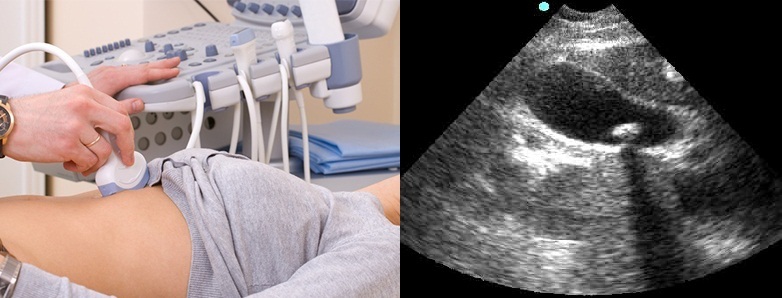

Диагностика калькулезного холецистита в типичных случаях не представляет особых сложностей. Жалобы, анамнез, пальпация, перкуссия…и, для подтверждения, УЗИ органов брюшной полости, как золотой стандарт диагностики ХКХ. При данном исследовании можно обнаружить особенности строения пузыря и протоков, увеличение толщины стенок пузыря, их расслоение, наличие камней в пузыре и протоках и их количество, размер.